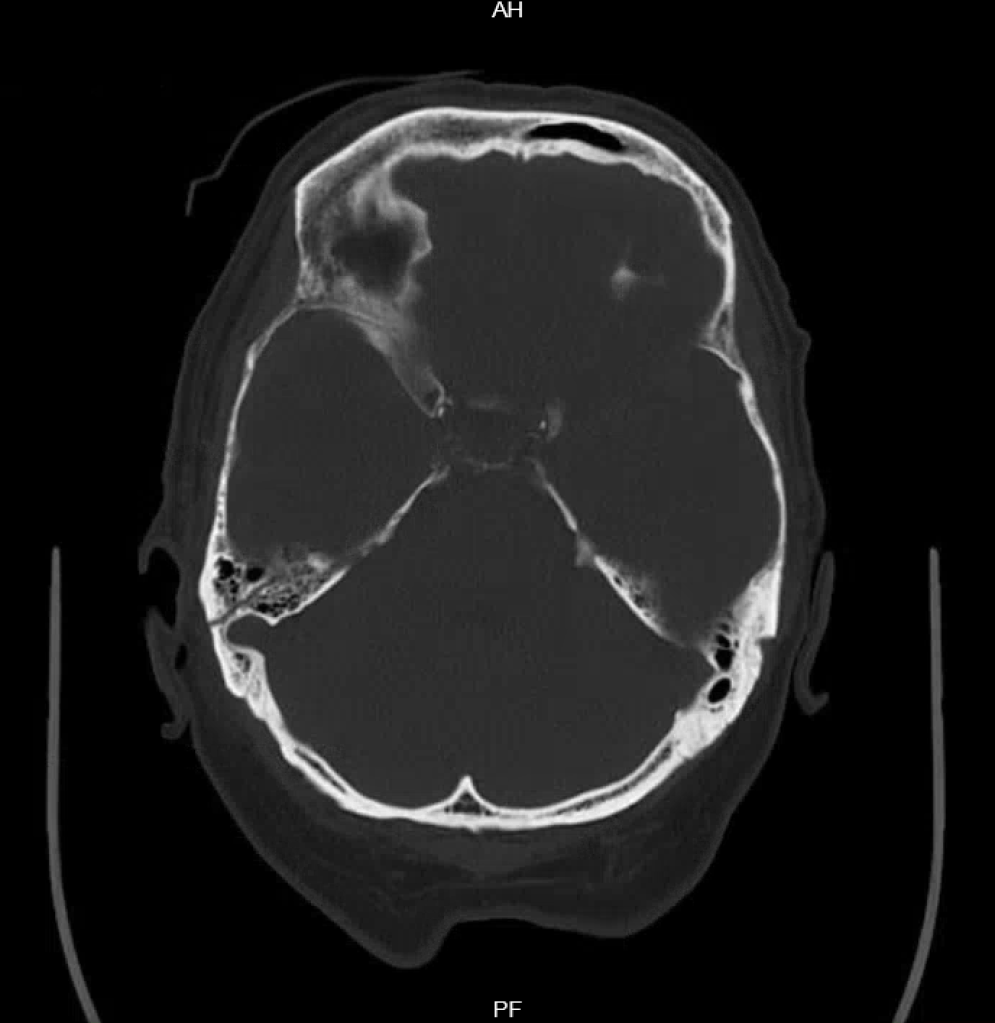

Seltene Befunde: Epiduralhämatome und diffuses axonales Trauma

Praktisch nur bei schweren Schädelhirn-Traumen sieht man Epiduralhämatome (EDH) und das diffuse axonale Trauma (DAT). Entsprechend kann ich hier leider keine bildgebenden Befunde aus dem eigenen Fundus präsentieren. Wie schon bei den großen Kontusionsblutungen gilt, dass das Vorhandensein von Epiduralhämatomen oder eines diffusen axonalen Traumas mit einer schlechten Prognose einhergeht.